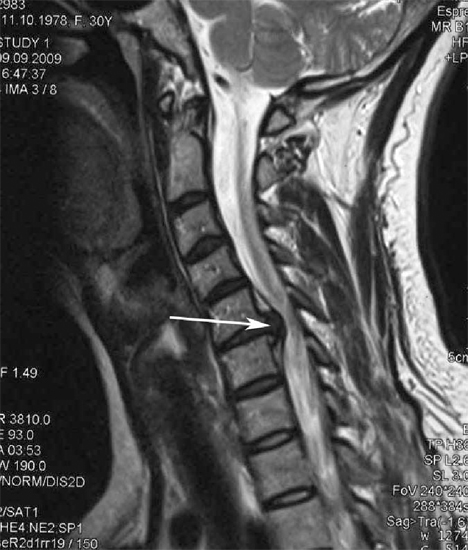

Стенозом позвоночного канала называют уменьшение его размера в передне-заднем направлении, а также уменьшение его ширины. Сужение позвоночного канала в шейном отделе наиболее часто встречается при образовании межпозвонковых грыж, остеофитов (костных разрастаний в позвоночном канале), гипертрофии (утолщении) задней продольной связки, нестабильности позвоночника (Рис.1).

Рис.1. Магнитно-резонансная томография (МРТ) шейного отдела позвоночника в сагиттальной проекции. Стеноз позвоночного канала на уровне С5-С6 позвонков, обусловленный парамедианной секвестированной мп грыжей диска больших размеров (показана стрелкой). Кроме того, на уровне стрелки определяется кифотическая деформация шейного отдела позвоночника (описание см. в тексте).